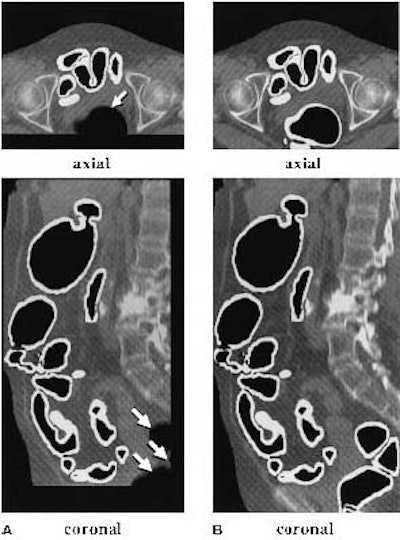

![]() |

| (A) The original anatomy-oriented colon segmentation (white region) could exclude small disconnected regions of the colon such as the rectum. (B) The improved anatomy-based extraction includes the rectum correctly in the segmented region. Note that in this example, the improved ABE produces a larger volume of interest to cover the entire colon. Image and caption reproduced courtesy of the Journal of Computer Assisted Tomography. |